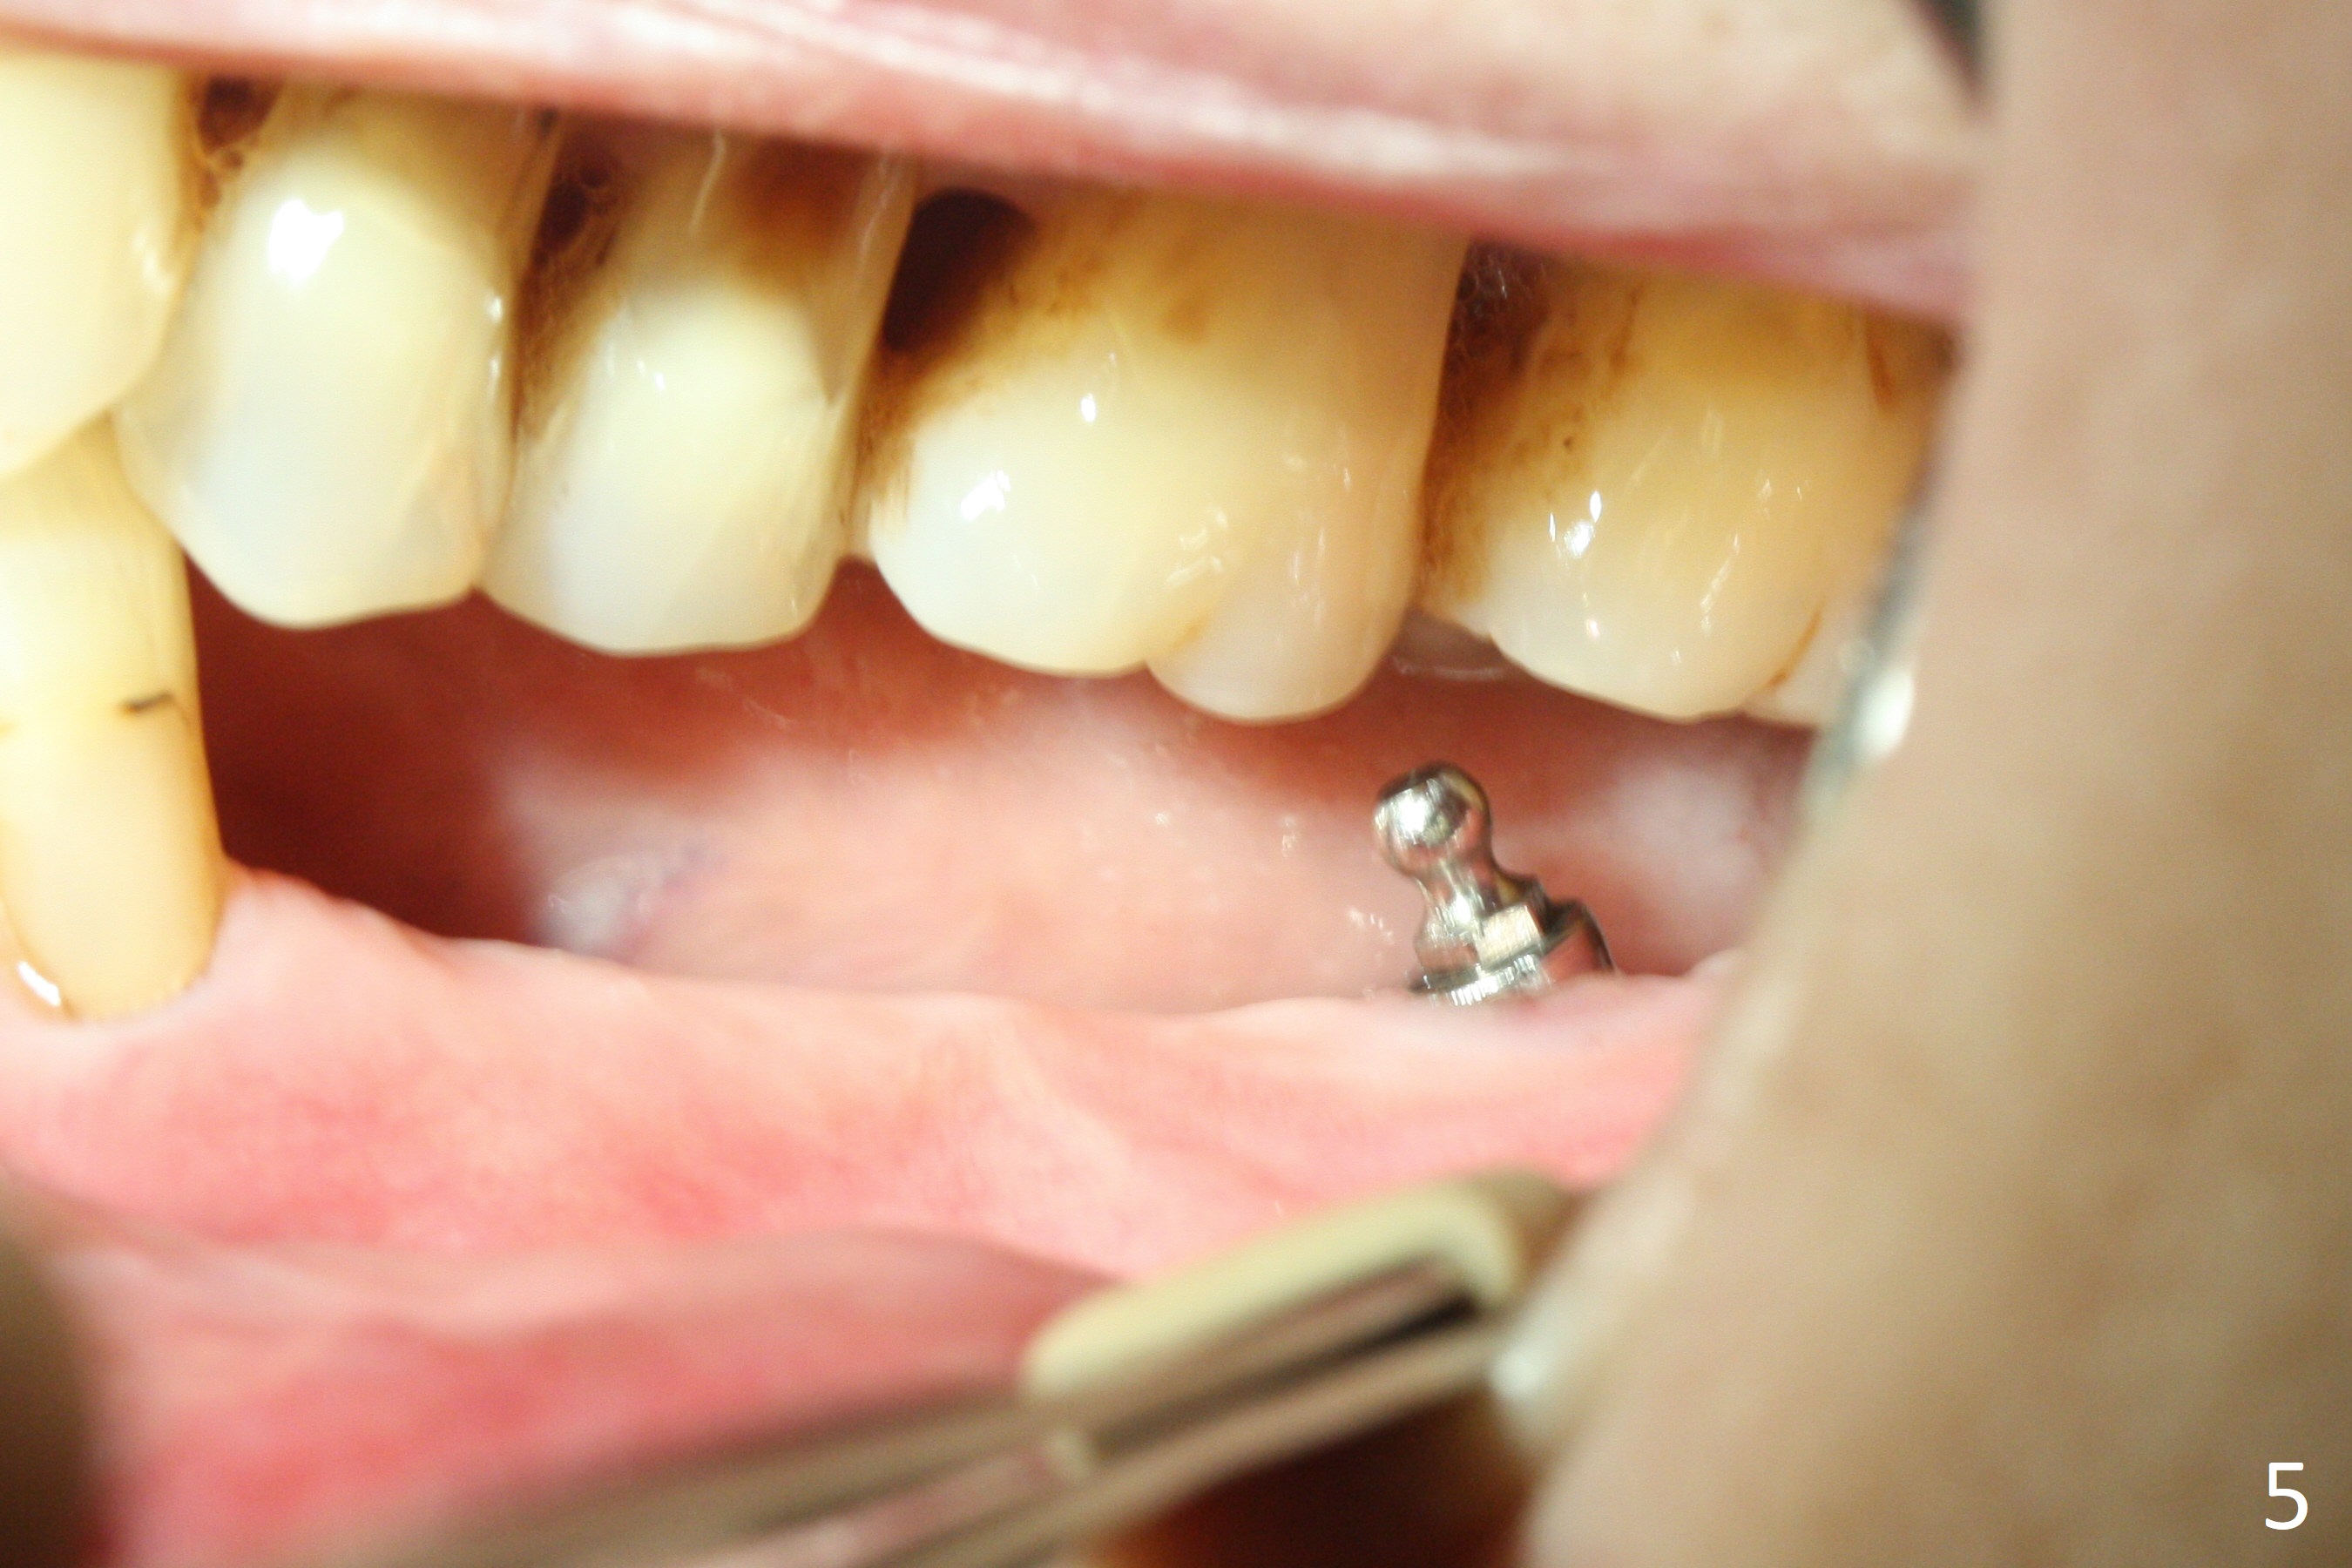

Preop photo confirms the lower left posterior pointed ridge (Fig.1). After ridge reduction and 2 mm drill for 8 mm, a parallel pin is inserted (Fig.2). A 3.8x8 mm SM implant is placed with >50 Ncm (Fig.3). The coronal threads (buccodistal) is covered with VeraGraft after placement of 4.1x5(3) mm healing abutment. The tooth #17 is not planned for extraction while the implant is osteointegrated. The tooth appears to be too loose and is extracted ~ 1.5 months postop. The implant seems to be osteointegrated 3 months postop (Fig.4). The healing abutment is changed to ball abutments with 4 mm (Fig.5) and 2 mm (Fig.6) cuffs. In fact the latter stays. What is the special device at the site of #18 (ring, Fig.7 <)?